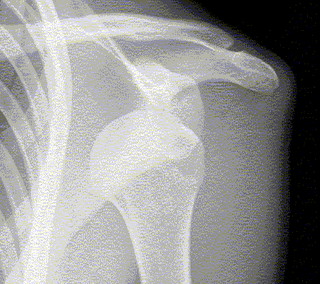

El tratamiento generalmente es la recolocación del humero en la articulación o “meter el hombro”, sin embargo siempre es recomendable realizar una Rx del hombre antes de hacer maniobra por el riesgo de fractura.